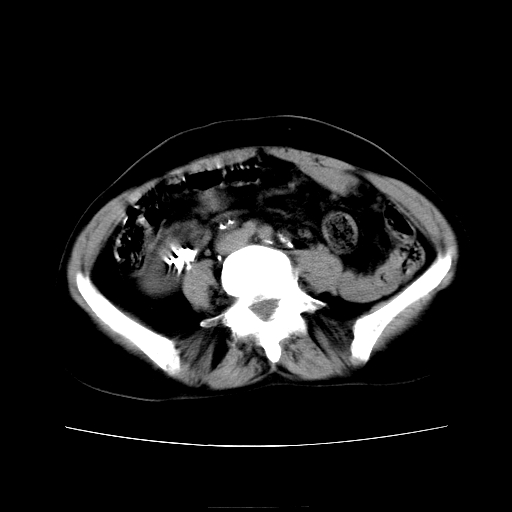

女45y多次(7次)碎石,结果不理想!曾碎石后尿出小碎石,仍腰痛,要求ct,其它不详.本人更倾向于钙化斑!无肾实质破坏,积水等提示集合系统无梗阻.另外腹腔多处钙化.是否结核后改变!谢谢赐教!

1)双肾结石。2)脾脏钙化灶。3)腹膜后多发淋巴结钙化。

尿路结石与腹部淋巴结钙化共存,建议v尿路造影检查,免得钙化灶冤枉为结石受罚。

考虑双肾结石,肾脏实质无破坏表现,没有结核病史,不考虑肾结核,